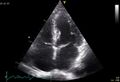

- BasicsOfImagingFig10.jpg 1,004 × 749; 49 KB

- BasicsOfImagingFig11.jpg 1,000 × 748; 45 KB